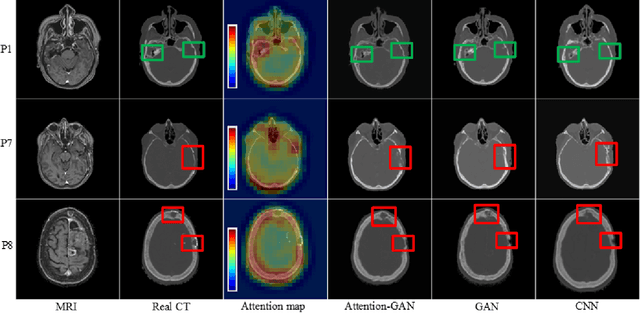

Abstract:Recently, interest in MR-only treatment planning using synthetic CTs (synCTs) has grown rapidly in radiation therapy. However, developing class solutions for medical images that contain atypical anatomy remains a major limitation. In this paper, we propose a novel spatial attention-guided generative adversarial network (attention-GAN) model to generate accurate synCTs using T1-weighted MRI images as the input to address atypical anatomy. Experimental results on fifteen brain cancer patients show that attention-GAN outperformed existing synCT models and achieved an average MAE of 85.22$\pm$12.08, 232.41$\pm$60.86, 246.38$\pm$42.67 Hounsfield units between synCT and CT-SIM across the entire head, bone and air regions, respectively. Qualitative analysis shows that attention-GAN has the ability to use spatially focused areas to better handle outliers, areas with complex anatomy or post-surgical regions, and thus offer strong potential for supporting near real-time MR-only treatment planning.